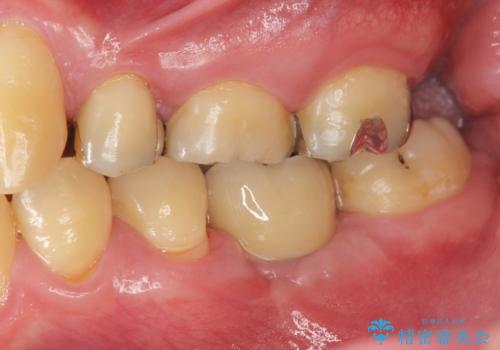

インプラントによる咬合機能回復

- 「長年虫歯放置した結果、抜歯となってしまった左下奥歯に歯を入れたい」、と希望され来院されました。

前後の歯は虫歯も治療歴もないため、前後の歯を削らなくてはいけないブリッジではなくインプラント治療による咬合機能回復を計画します。

減ってしまった顎骨に増骨処置を行うことで、より安定した環境で長く使用できるようなインプラント治療を行っています。